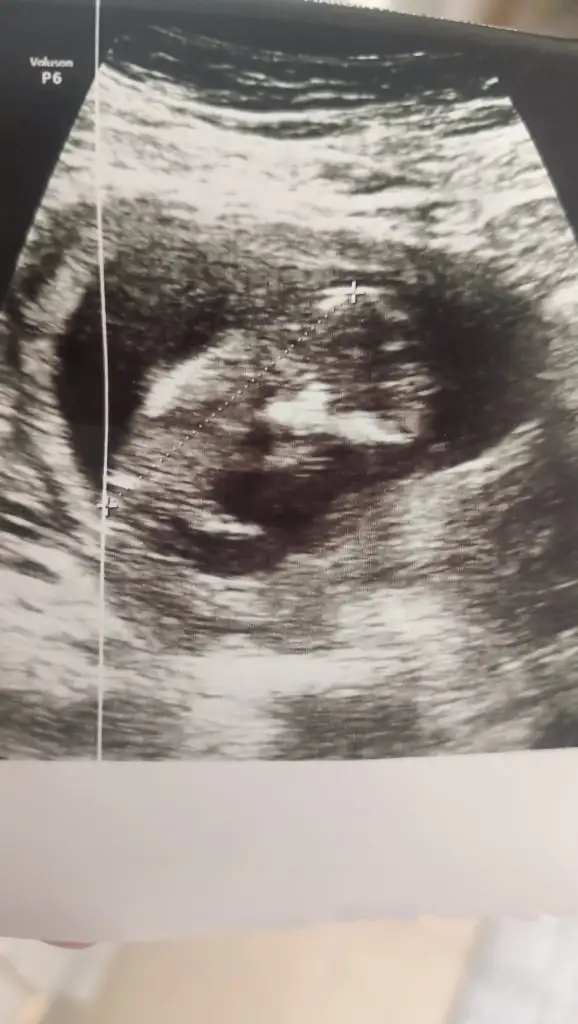

• 17134404379845450892110518396676.webp

17134404379845450892110518396676.webp

27,2 KB · Görüntüleme: 62